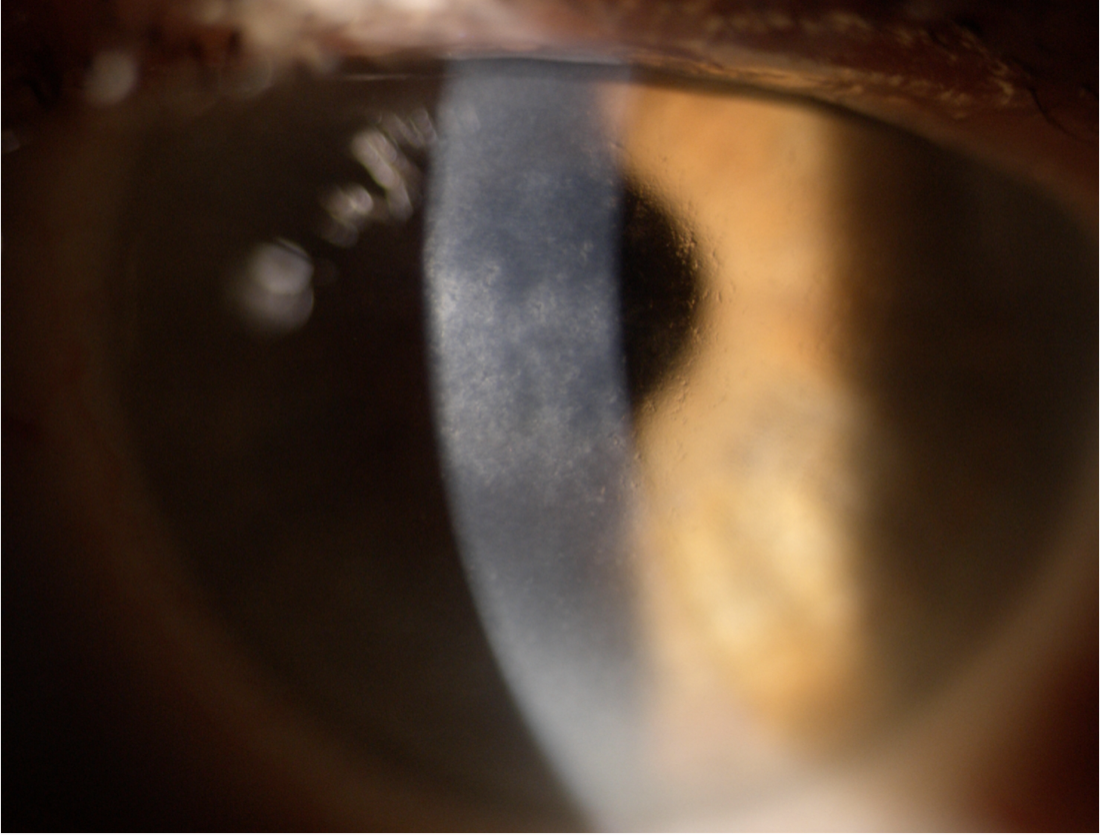

양안의 각막 기질 표층부에 격자형의 가치진 모양의 선이 발생합니다.

그리고 소결정의 혼탁이 발생하면서, 점점 격자 형태가 갖추어집니다.

각막의 중심부를 주로 침범하며, 주변부는 침범하지 않는 것이 특징입니다.